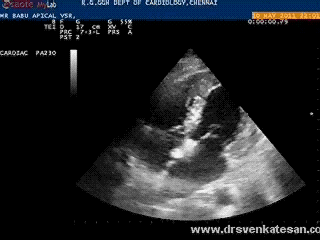

Mechanical complications are not rare  following acute MI .In fact , it closely competes with electrical deaths . Many times it is not recognised  and get wrongly labeled as  simple pump  failure .

Echocardiography has revolutionised the way , we approach these deadly complication.(Of course , many  deaths  could  not be prevented still !)

The rupture site is predetermined by the patients fate !. If the tear occur in free wall of LV  , in all likely-hood ,we are going to lose the patient. If he is blessed  , the rupture take place in the interventricular  septum .Here , the issue is less disastrous as the  blood is  simply shunted to a different chamber .In fact , some consider VSR puts an ailing ventricle at  a slight hemodynamic advantage which is referred to as decompression .   The LVEDP has  a biphasic response to VSR  .An  initial raise bfollowed by a flat response.This has a clinical correlation too  with a temporary deterioration and subsequent stabilisation.

An irregular tear in the mid ventricular septum

This patient did well with initial medical support and referred for surgery electively